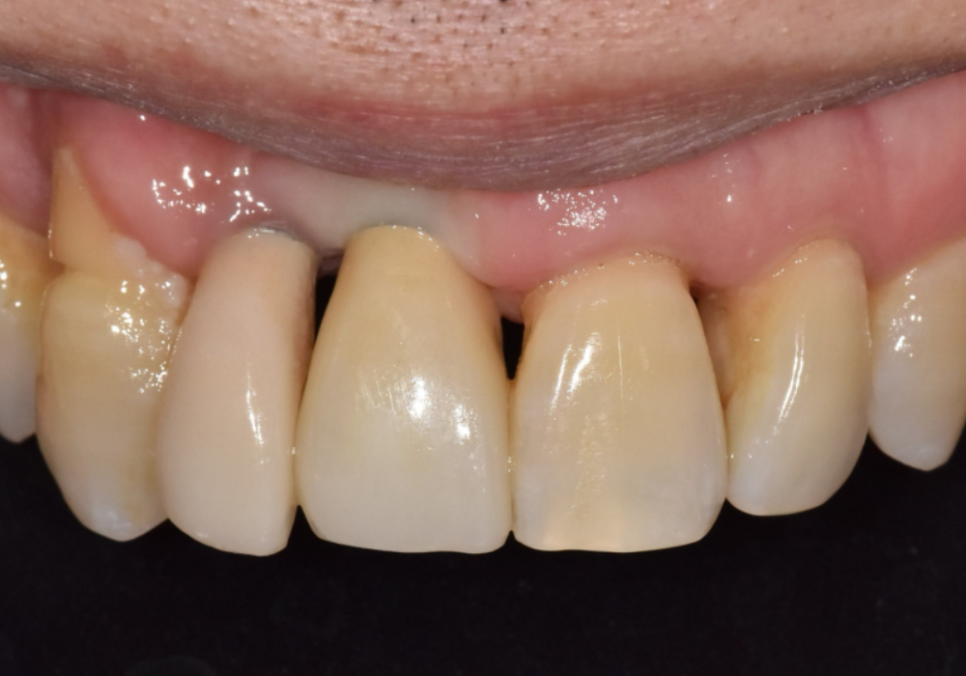

얼마 전 앞니 흔들림으로 찾아주신

환자분의 사례를 통해

조금 더 쉽게 설명해 드릴게요.

내원 당시 오른쪽 앞니(#12)가

심하게 흔들리고 있었고,

바로 옆 중앙 앞니(#11)도

잇몸뼈가 많이 내려가 영향을 받고 있었습니다.

일단 흔들림이 심한 오른쪽 앞니(#12)만

발치하고 임플란트를 진행했습니다.